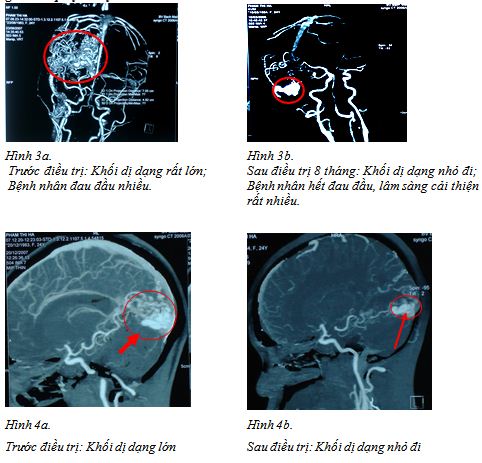

Bệnh nhân Phạm Thị H nữ 24 tuổi, chẩn đoán: AVM vùng chẩm, xạ phẫu dao gamma quay 18Gy

Bệnh nhân nam, 37 tuổi, vào viện vì xuất huyết não, chẩn đóan: AVM vỡ. Bệnh nhân được xạ phẫu liều 20Gy.